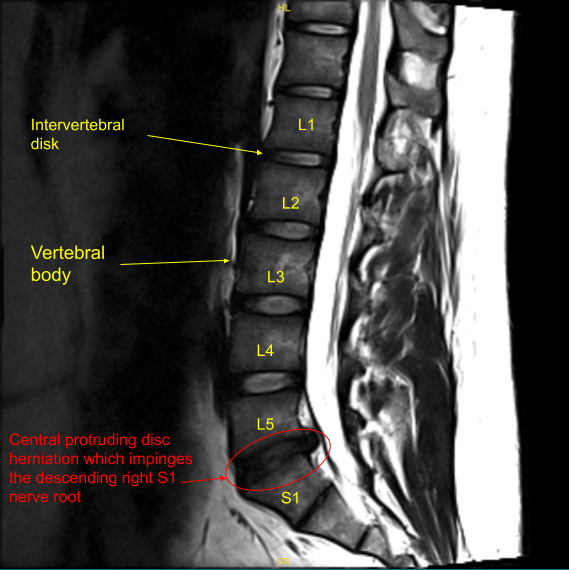

The patient had a radiating pain along the back of the right thigh and leg into the sole of the foot for which they were seeing me as an outpatient. We got an MRI, which showed disc herniation and compression of the right S1 nerve root. We discussed treatment options. The patient tried Medrol-Dosepak, which did not help.